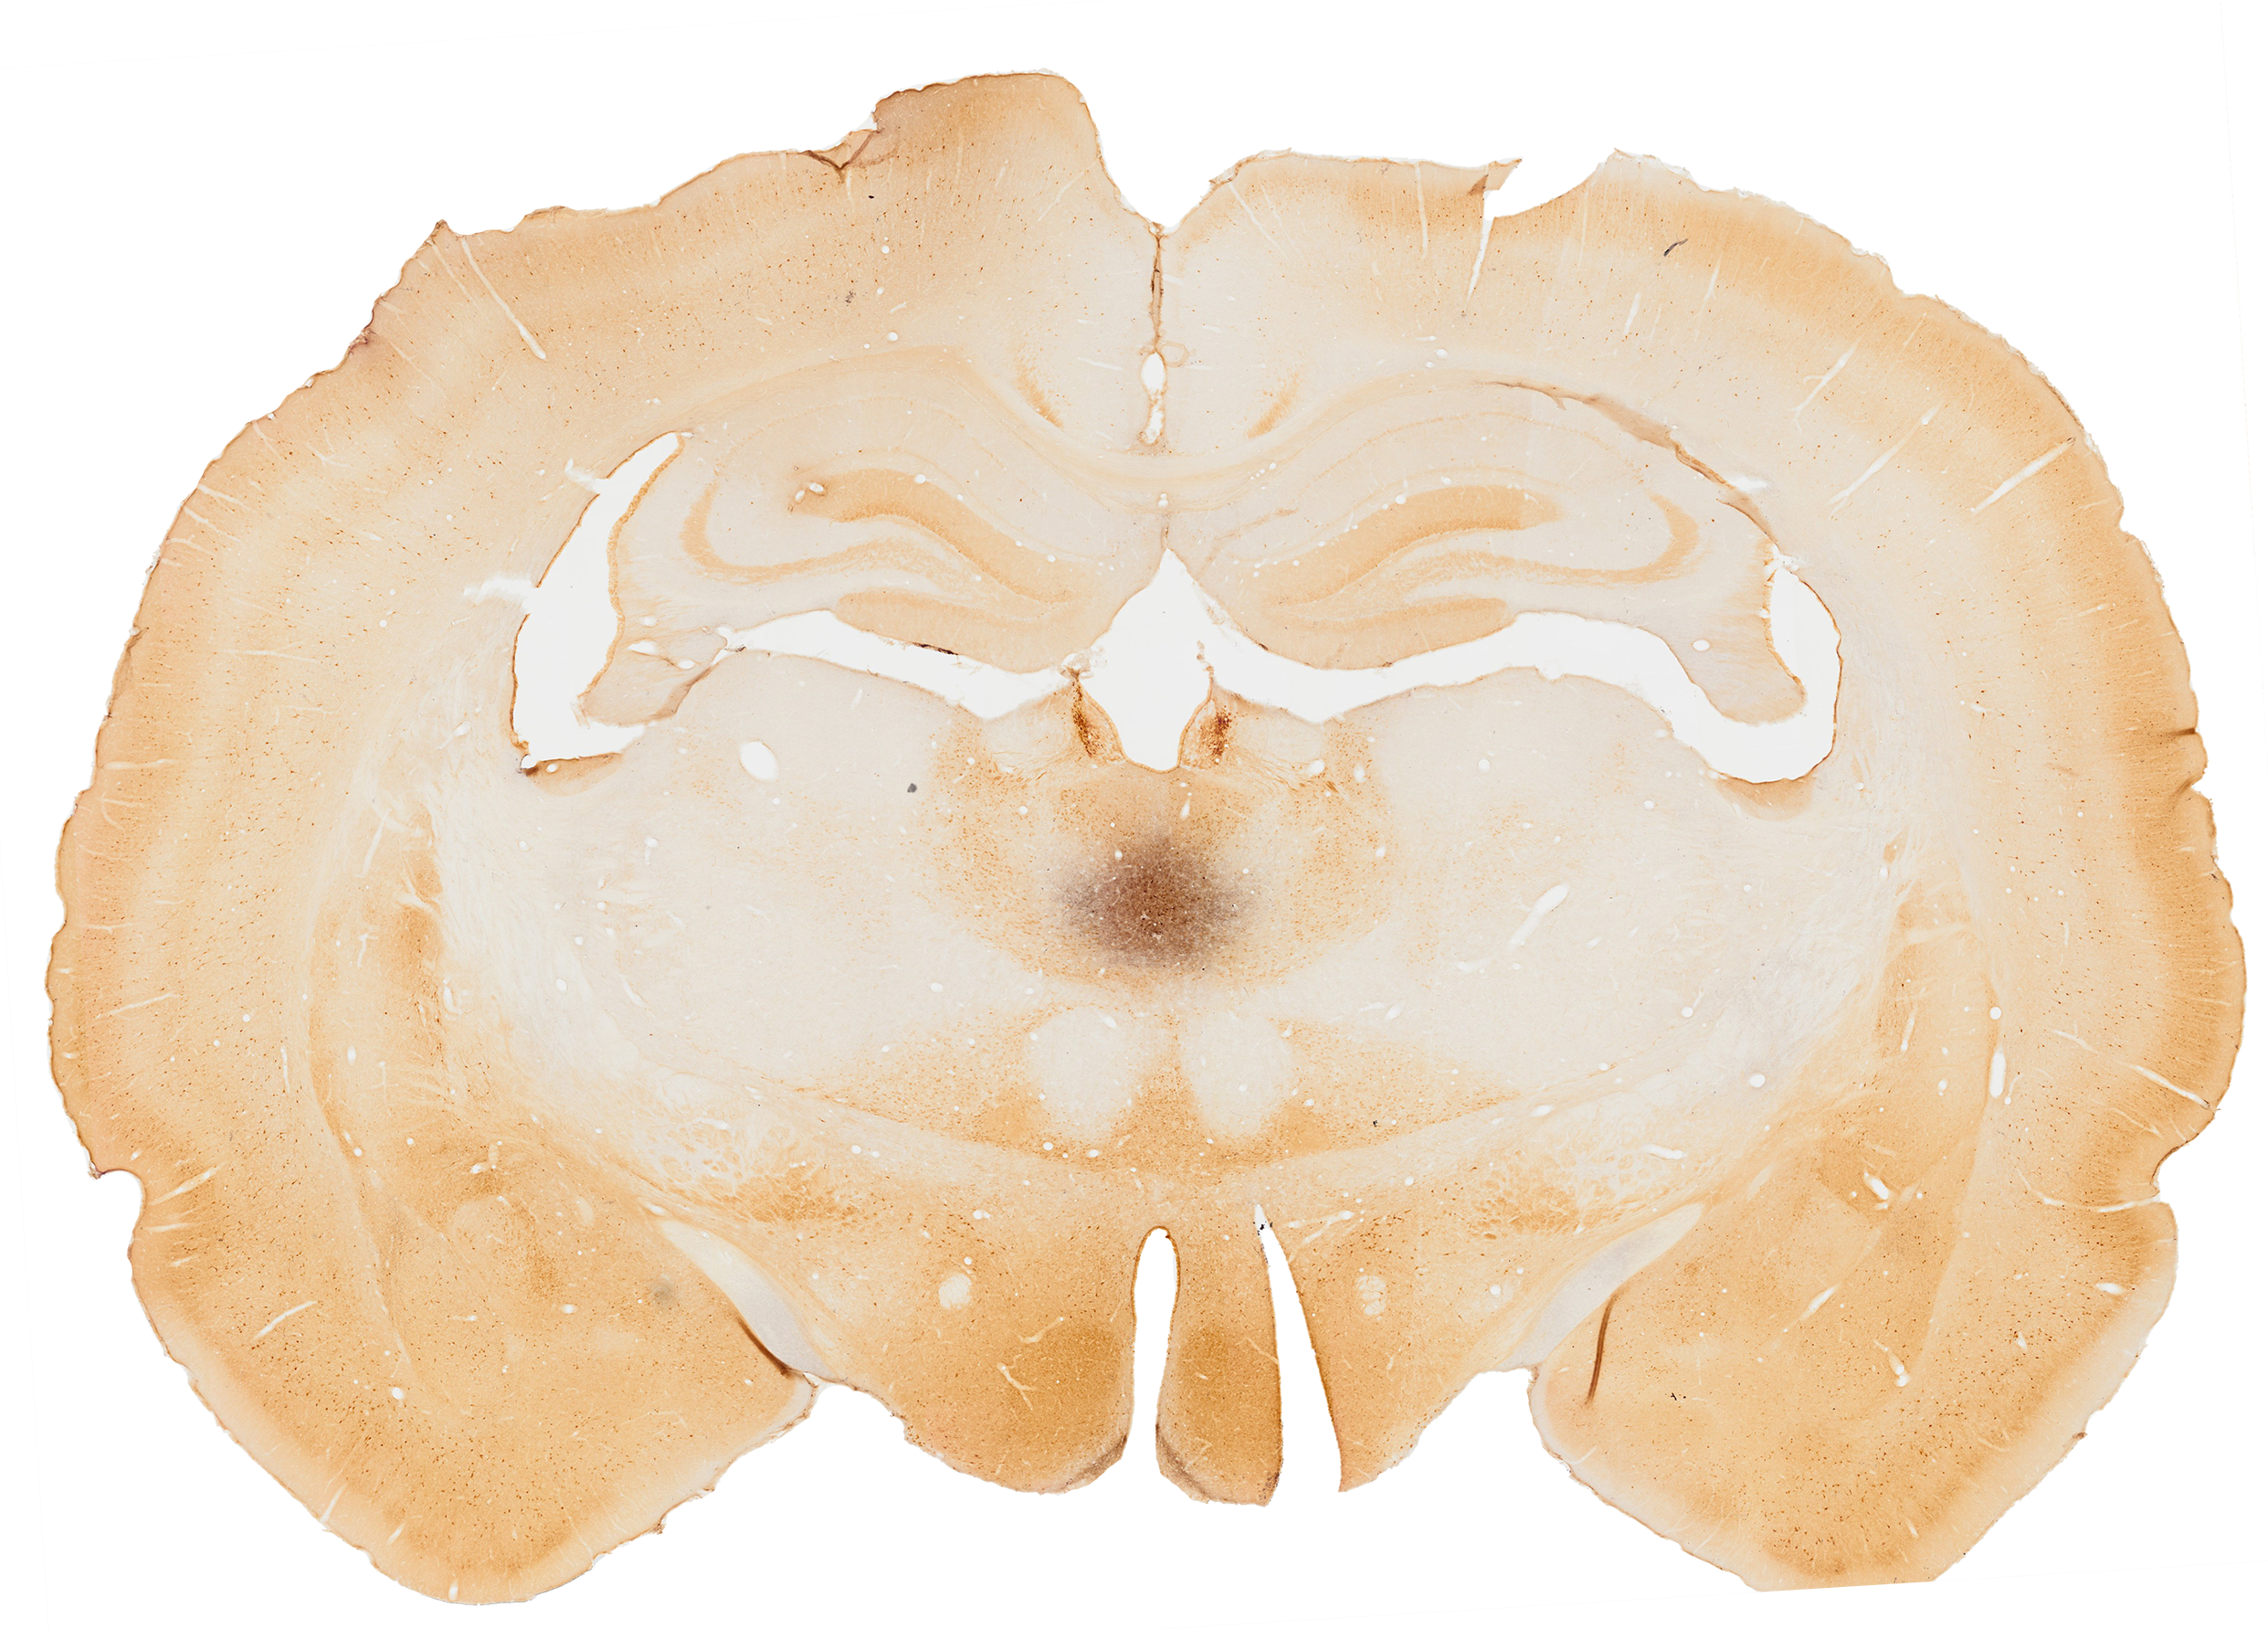

Limbic System

The limbic system consists of an organization of complex neurochemical pathways which are involved in several emotional and motivational processes.1

Amygdala

The amygdala is a part of the limbic system that consists of a collection of nuclei that are located in the temporal lobe. It plays a role in emotional learning,2 social cognition,3 memory and attention.2

Hippocampus

Thalamus

The thalamus is located in the dorsal part of the diencephalon. It is referred to as the big information center of the brain, since it relays all incoming information to the cortex.4 The medial dorsal nucleus, the anterior nucleus, and the lateral dorsal nucleus are considered to be part of the limbic system.4

Prefrontal Cortex

The prefrontal cortex is a brain structure that covers the front part of the frontal lobe and the cortex. It is highly connected to the limbic system and it is involved in executive functions, language and emotional processing.5